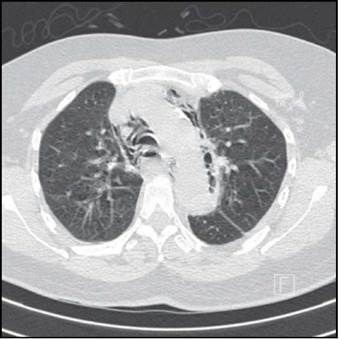

Mujer de 58 años, ingresa a urgencias por presentar dolor pleurítico en hemitórax izquierdo de fuerte intensidad, irradiada a dorso, asociado a tos seca y disnea progresiva. No tiene antecedentes de importancia. Al ingreso con tensión arterial: 80/46 mmHg, frecuencia cardiaca 112 por minuto, frecuencia respiratoria: 22 por minuto y temperatura: 39°C. Al examen físico: disminución del murmullo vesicular basal izquierdo con estertores y llenado capilar prolongado. Se toman laboratorios que muestran leucocitosis, neutrofilia y elevación de azoados. Se solicita radiografía de tórax que muestra consolidación basal izquierda y enfisema subcutáneo en cuello. Es trasladada a unidad de cuidados intensivos con choque séptico de origen pulmonar. Al reinterrogar a la paciente refiere episodio de atoramiento alimentario previo al inicio del cuadro, acompañado de múltiples episodios eméticos. Se sospecha síndrome de Boerhaave (perforación esofágica espontánea) y mediastinitis aguda, obteniéndose esofagograma que evidencia hallazgos compatibles con perforación esofágica distal (Figura 1) y tomografía de tórax que muestra neumomediastino y derrame pleural con consolidación basal izquierda (Figura 2), por lo cual se instaura vancomicina y piperacilina tazobactam. Es llevada a cirugía donde encuentran perforación de esófago torácico (Figura 3), con mediastinitis, pericarditis y pleuritis izquierda. No fue posible cirugía definitiva ante la inestabilidad de la paciente, únicamente se realizan drenaje de material purulento mediastinal, pleural, pericárdico y colocación de tubo en mediastino y tórax. A las 24 horas se realiza esofaguectomía media y distal con esofagostomía proximal cervical. Evoluciona tórpidamente, se documenta bacteriemia por Serratia marcescens resistente, se indica meropenem. Luego de múltiples lavados mediastinales, ventilación mecánica prolongada y 45 días en unidad de cuidados intensivos, progresa a falla orgánica múltiple y fallece.